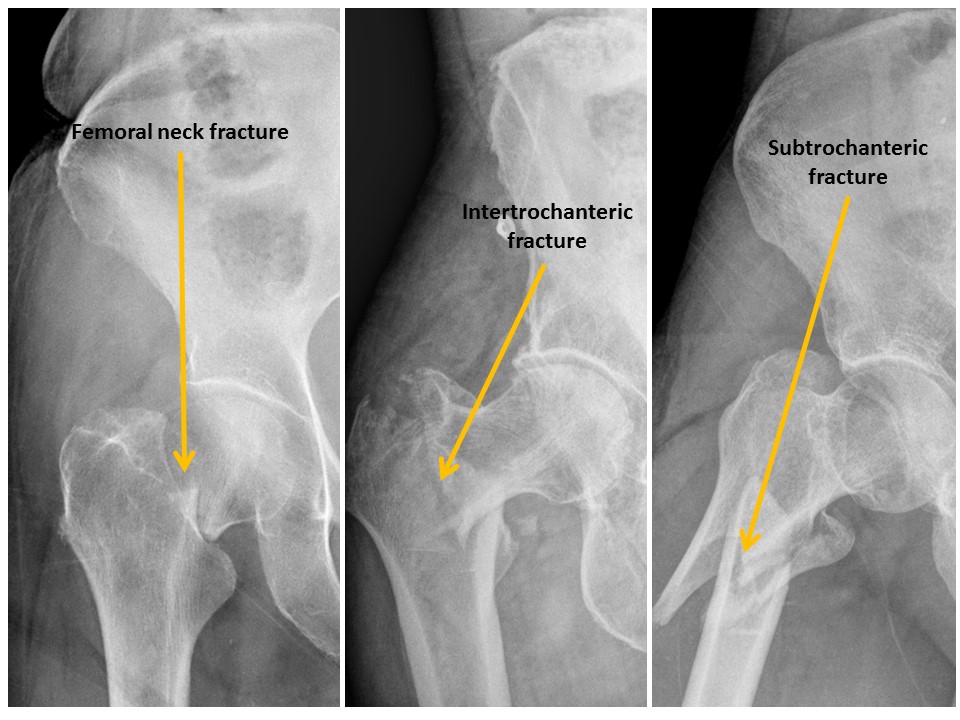

There are fractures of the femoral neck, intertrochanteric region, or subtrochanteric region. |

Yes | NA |

There are avulsion fractures of the greater or lesser trochanters. |

Fracture of the left greater trochanter. Underlying masslike lucency is concerning for pathologic fracture.

CT to further evaluate for underlying pathologic fracture.

Urgent: non-routine communication within 4 hours